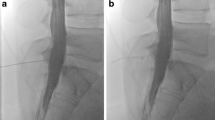

Patients were divided into 4 groups: (1) SLEC(+): patients with SIH and SLEC confirmed on multimodal imaging including spine MRI, conventional dynamic myelography (CDM) and PMCT (Fig. 1), (2) SLEC(−): SIH patients without SLEC on multimodal spine imaging (Fig. 1), (3) control group 1: consecutive patients seen during a 3-month period, without orthostatic headache, in whom CT myelography was performed to rule out spinal cord or nerve root compression, (4) control group 2: patients without orthostatic headache who underwent unenhanced CT of the spine for unrelated indications and were used as a reference standard for the study evaluation but not further evaluated.

Patient with orthostatic headache. a, b Brain MRI demonstrating pachymeningeal enhancement (a; black arrows), venous engorgement (a; white arrow), no subdural collection, effaced suprasellar (< 4.0 mm) and prepontine (< 5.0 mm) cistern, and decreased mamillopontine distance (< 6.5 mm); SIH score = 8 indicating high likelihood of SIH. c, d Spine MRI does not show a spinal longitudinal extradural CSF collection; however, multiple spinal nerve root cysts are demonstrated. e, f Conventional dynamic myelography and postmyelography CT demonstrate filling of the nerve root cysts without epidural contrast agent leakage or a CSF venous fistula. CSF cerebrospinal fluid, CT computed tomography, MRI magnetic resonance imaging, SIH spontaneous intracranial hypotension